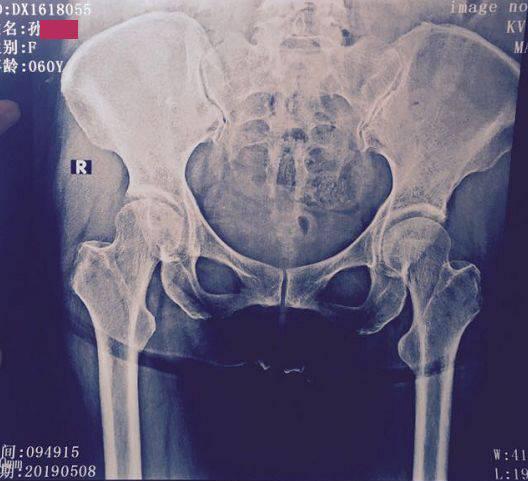

思緒回到一年前,醫院根據檢查結果判定我股骨頭壞死已經到了Ⅳ期,我不得不從單位離職,離開自己喜歡的崗位,萬般不舍。在那之前的半年時間里,我一直在治療,但是病情不但沒有好轉,還越來越嚴重,已經從最開始的間歇性疼痛,發展為走幾十米的路都要停下來休息的地步,不扶東西站著都有點吃力。

第二天如約而至,我懷著忐忑的心情接通了醫助老師打過來的視頻電話,預約的大夫通過視頻問診詢問了我一些問題,例如睡眠情況,二便如何,以及一些檢查結果等,我都一一如實回答,接著看了我的舌苔情況,并讓我在問診結束后,把各項檢查單和磁共振片子都發給他的助理。

后來又堅持用了第二個周期,我的病情一天天好轉,去醫院拍片檢查,我的病情已經降為Ⅱ級了,除了偶爾會有隱隱作痛的感覺,大部分時間我都感覺自己像個正常人一樣了,因為擔心復發,我又接受了鞏固治療。